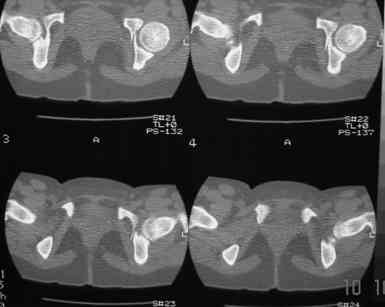

В больнице вправили вывих бедра, три недели на вытяжении. Беспокоят боли в левом тазобедренном суставе и левом крестцово-подвздошном сочленении. Ходит с тростью. Снимок - в приложении. Направил на КТ, заключение: разрыв симфиза и левого крестцово-подвздошного сочленения, переломы крыши и заднего края вертлужной впадины, горизонтальной ветви лонной кости слева.

Уважаемый д-р Булахтин, на мой взгляд единственное повреждение требующее синтеза - застарелый разрыв лона. Низкий перелом передней колонны безопасен, повреждения свода не вижу, неясно что было сзади (скорее боковая масса)лучше сделать обзорный снимок прямой и Inlet.

Очень похоже на повреждение от бокового сжатия.

Если был задний вывих, то повреждение должно локализоваться сзади. В данном случае перелом спереди, как результат сдавления лонного сочленения.

Синтез лонного сочленения восстановит стабильность тазового кольца.

А вывих можно вести не обращая внимания на перелом.

Не наступать на ногу 3 месяца.

АНГБК развивается далеко не у всех, даже после больших реконструктивных операций и в застарелых случаях. Если вывих вправлен в первые 6 часов, шансы на успех вообще больше 90%.